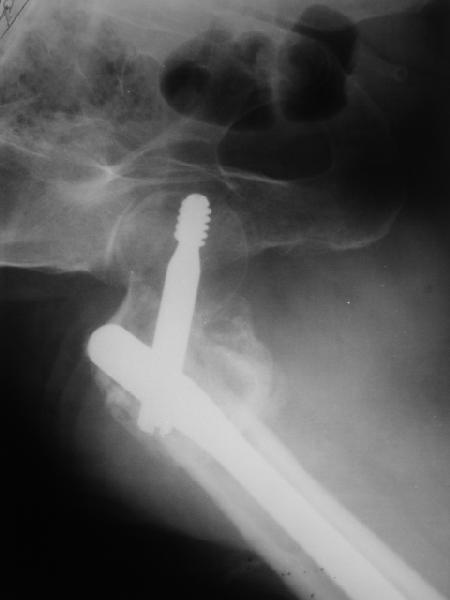

По опыту подобных случаев, аппарат лучше на бедро, без таза пока. В проксимальный фрагмент 3 стержня по оси шейки. Дистальный - хватит 1 стержня или 2 спиц в дистальном метафизе и 1 стержня вверху. Если планируете гвоздь, надо с гиперкоррекцией восстановить длину и ось, т.е. вальгизировать проксимальный отдел. При наложении аппарата сделать остеоклазию, добиться уверенной подвижности. Регенерат не нужен, тяните на пределе переносимости пациентом - хоть 2 см/сут. Обычно меньше.

Второй этап - на следующий день после окончания коррекции.

Если все получилось, т.е. закрыто сопоставить с гиперкоррекцией, накладываете дистрактор таз-бедро или используете тракционный стол, и гвоздь можно делать закрыто. Пластика то есть не нужна. Если клинковая пластина - может получиться как при меежвертельной остеотомии, боковая компрессия by mismatch. Тогда тоже пластика не нужна. Если не получатся, можно и сделать.

В приложении пример пациента, близкого по картине к тому, что представил Виктор (варус и смещение периферического отломка на поперечник кзади). Сделали как раз то, что Виктор исходно намеревался - аппаратная коррекция и затем гамма.